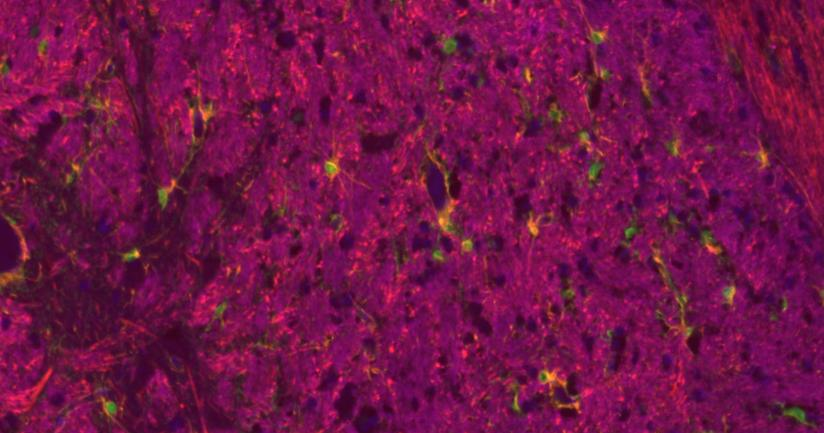

人脑组织

大鼠脑组织

小鼠脑组织

使用抗体

Target Catalog # Product Name

MBP bs-24827R MBP Rabbit pAb

GFAP bs-0199R GFAP Rabbit pAb

NF-L bs-41217R NF-L Rabbit pAb

S100B bsm-10832M S100B Mouse mAb